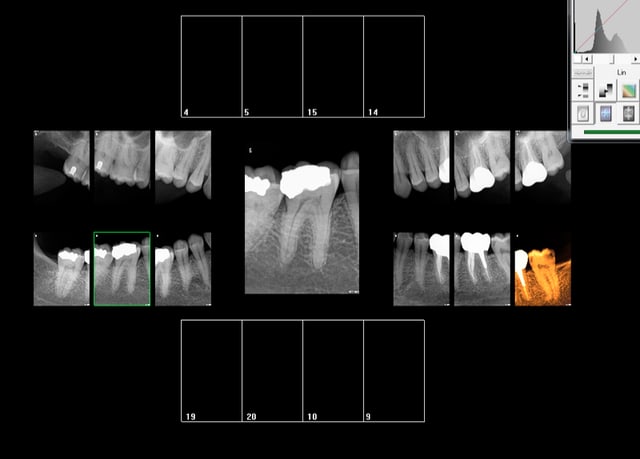

Rebelote aujourd'hui. Pulpite sur 15.

Re re belote. pulpite 38. -))))

Pas venu depuis 2007 date de la pose d'onlays sur 45 46.

On va pas refaire le débat, mais ou bien je suis un mutilator, ou bien je suis lobotomisé, mais il ne me semble pas aberrant de poser IC/Cr sur cette 15 non ?, je me vois pas y coller un onlay.

Après Chicot, on a les mêmes qui consultent quand ça picote sérieux, et en général l'indication du coiffage MTA,biodentine/inlay/onlay, n'est plus vraiment d'actualité.

En général c'est déjà limite pour la couronne alors ...

Suivant : 47 pétée en distal mais pas de douleur ( dernier RDV 2008) . Chiotte elle pouvait pas attendre un peu avant de péter ? j'aime bien les actes qui solvabilisent à la fois le patient et le praticien pas ces soins opposables à un tarif de merde. -)))

Ah ! enfin une endo au résultat non aléatoire sur 36 ! spéciale dédicace pour améli ! -))))

Suivant : 45 cassée ( jadis un onlay support de bridge ? ) Dent gardée vivante puis endo à travers l'onlay je suppose. ca marche moins bien après forcément. -))))

Maintenant la question que je me pose , vais je continuer à soigner les caries moyennes révélées ailleurs par les radios ? Vu qu'on nous prend pour des cons, hein ?

En plus faire les radios et les coter c'est prendre le risque de se faire emmerder par un CDC, autant ne plus en faire non ? ca résoud le problème de conscience que je pourrais me poser à l'avenir ! Il suffira d'attendre les signes d'appels et d'avoir des stocks de R25 ! -))))

Suivant : douleurs 36. Abcès du à un Syndrome du septum dent vivante, dommage.......-)))))

Dernier rendez vous chez le dentiste : 12 ans ( extractions des sagesses)

Notez l'indication des rétro coronaires et de la rétro alvéolaire dans ce cas : pas d'antécédents de soins intensifs et atteinte pulpaire suspectée ( élimination d'un 4ième degré, fais le test au froid après) . -)))))